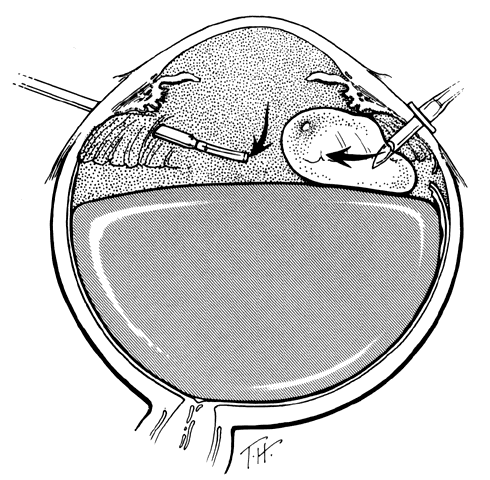

TECHNIQUE. With the tip of the vitrectomy probe or a retinal manipulator (i.e., an angulated probe with a ball-like tip), the inverted retinal flap is partially unfolded to expose the optic disc and posterior pole (Fig. 7). Perfluoro-n-octane is injected slowly through a blunt-tipped 25-gauge needle positioned 1 to 2 mm over the optic disc (Fig. 8), creating a globule. As the globule expands toward the fundus periphery, it smoothly unfolds the posterior retinal flap. To prevent the formation of multiple bubbles of perfluoro-n-octane, the tip of the injection needle must be kept within the globule during injection.

Fig. 7. The posterior retinal flap is partially unfolded with a ball-tipped retinal manipulator. (Freeman HM: Current management of giant retinal breaks and fellow eyes. In Glaser BM, Ryan SJ(eds): Surgical Retina, 2nd ed, pp 2313–2338. St. Louis, CV Mosby, 1994)

Fig. 8. Perfluoro-octane (PFO) is injected through a blunt-tipped 25-gauge needle positioned 1 to 2 mm in front of the optic disc. (Freeman HM: Current management of giant retinal breaks and fellow eyes. In Glaser BM, Ryan SJ (eds): Surgical Retina, 2nd ed, pp 2313–2338. St. Louis, CV Mosby, 1994)

If epiretinal membranes are causing the posterior edge of the flap to roll or curl, they can be removed as follows. An injection of 0.8 to 1 mL perfluoro-n-octane is used as a means of partially unfolding the flap and steadying it to enable bimanual dissection of the epiretinal membranes. After the membranes are removed, additional perfluoro-n-octane is injected to bring the level of the perfluoro-n-octane to the posterior edge of the giant tear (Fig. 9).